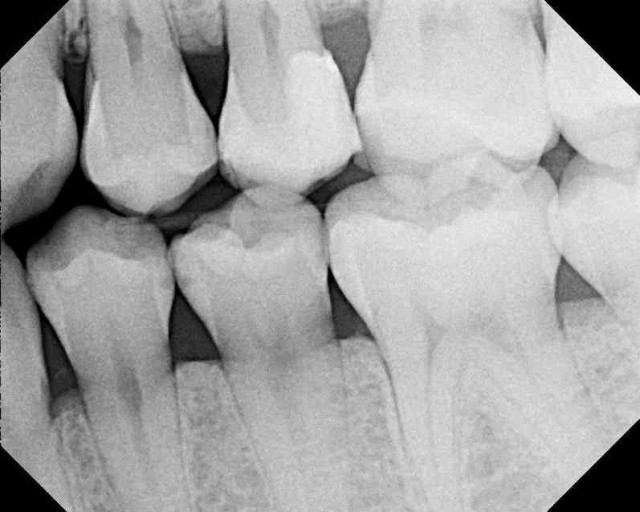

Patient 2: Tooth #28

A similar situation with a different patient, this time with caries to the DEJ. Caries were verified under the mesial of #29 as well and were more severe.